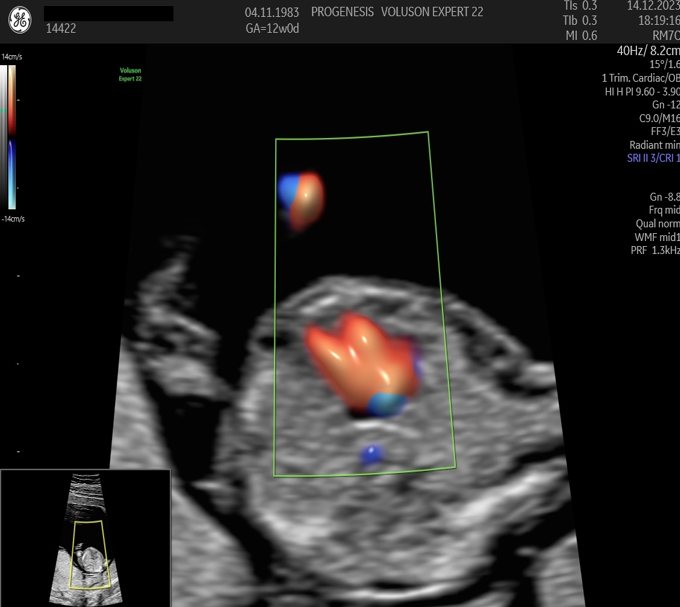

Πολλές και σημαντικές ανωμαλίες, όπως ανεγκεφαλία, απουσία άκρων, ομφαλοκήλη, ορισμένες συγγενείς καρδιοπάθειες και άλλες ανωμαλίες, είναι ορατές απ' αυτό το στάδιο της κύησης. Δίνουμε ιδιαίτερη έμφαση στην αξιολόγηση της καρδιάς των εμβρύων, τόσο για την αξιολόγηση χρωμοσωμικών ανωμαλιών όσο και πρώιμη ανίχνευση συγγενών καρδιοπαθειών από το 1ο κιόλας τρίμηνο (π.χ. υποπλασία καρδιάς, συγγενή μετάθεση μεγάλων αγγείων).